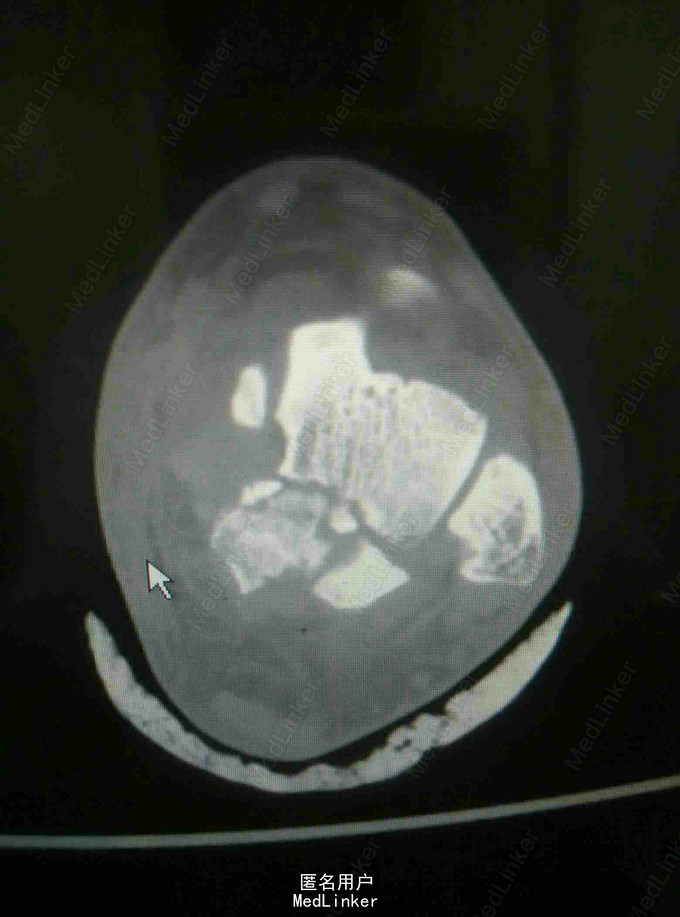

查体:左踝关节肿胀明显,局部皮肤压痛,无皮损及皮下淤斑,踝关节活动受限,各足趾感觉正常,足背动脉搏动存在。 辅查:我院CT提示距骨、足舟骨、跟骨骨折

诊断:左足距骨、足舟骨、跟骨骨折 治疗:距骨骨折切开复位内固定术

随访:石膏固定4-6周,3月内禁止负重,定期复查。 讨论:患者X线片对左足骨折显示不够清楚,基本常规行CT,可以看到明显的距骨骨折,累及关节面,需手术复位关节面。足舟骨以及跟骨骨折未明显移位保守处理。